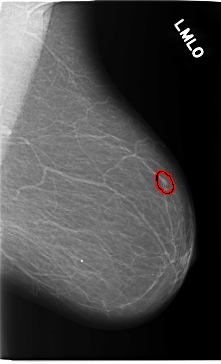

C_0119_1.LEFT_MLO

LEFT_MLO LINES 5816 PIXELS_PER_LINE 3536 BITS_PER_PIXEL 12 RESOLUTION 50 OVERLAY

FILE: C_0119_1.LEFT_MLO.OVERLAY

TOTAL_ABNORMALITIES 1

ABNORMALITY 1

LESION_TYPE MASS SHAPE OVAL MARGINS CIRCUMSCRIBED

ASSESSMENT 4

SUBTLETY 3

PATHOLOGY MALIGNANT

TOTAL_OUTLINES 1

BOUNDARY